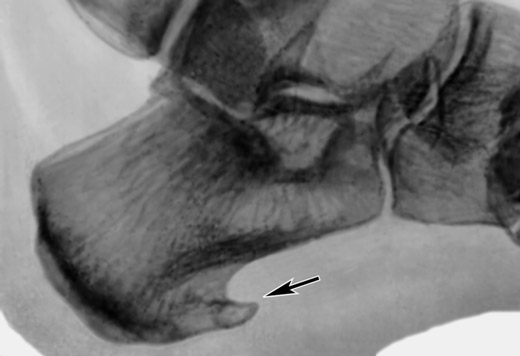

Перед проведением процедуры, проводится диагностика пациента – необходимо сделать рентгенологический снимок конечности. Рентгенограмма дает вид ноги в двух проекциях. По снимку врач определяет необходимость облучения, его периодичность, количество сеансов, нужных для получения результата. Интервал между сеансами обычно составляет от двух до нескольких дней.

После окончания восстановительного периода следует сделать повторно рентгеновский снимок, чтобы оценить наличие признаков шпоры.